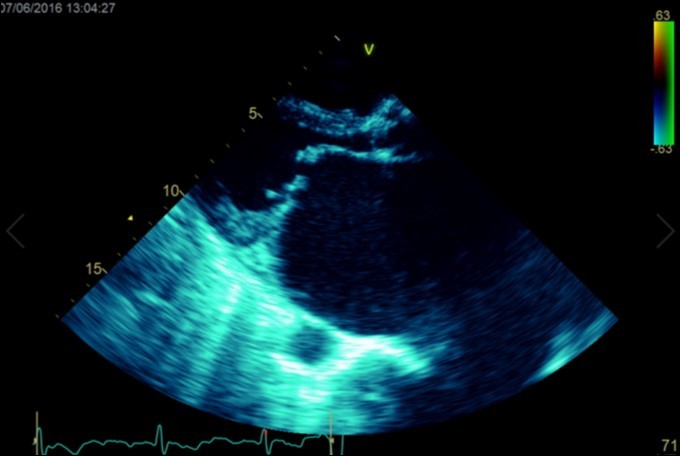

A dramatically dilated left atrium was seen on a TTE (see Figure 2a, Figure 2b, Figure 2c, and Figure 2d). Severe mitral stenosis with associated regurgitation was evident, with a mean gradient across the valve of 11mmHg and a hyperdynamic left ventricle. The left atrial volume measured by Simpson’s biplane method (see Figure 2c) was 2108mL, or 1548.5 ml/m2, based on height 1.55 metres and weight 44 Kg. Normal left atrial volume in a woman is 16 - 34 ml/m21. The computed tomography scan (CT) chest AP view (see Figure 3) is also shown.

Figure 2b.Transthoracic echocardiogram Parasternal long axis view. Findings include severe mitral stenosis (‘hockey-stick’ appearance to mitral valves), raised left atrial pressure (interatrial septum fixed and bowed to right)